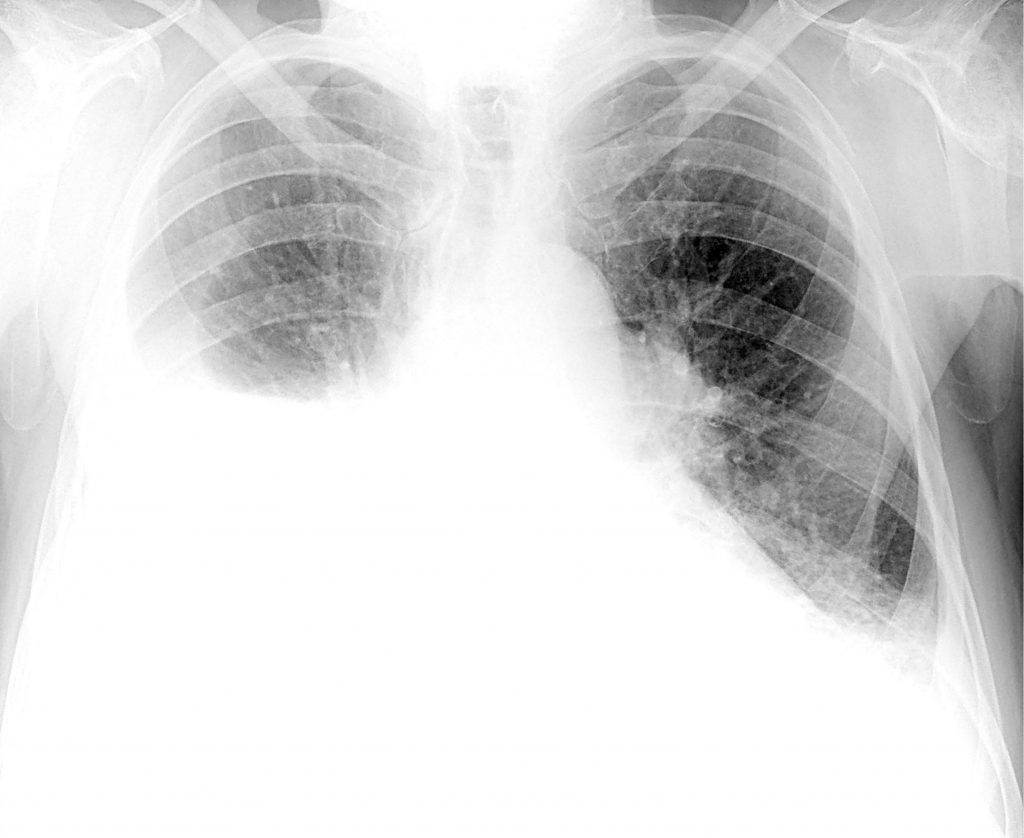

Изменения в легких при коронавирусе

Инфицирование новым штаммом вируса SARS-CoV-2 вызывает в органах дыхания острый воспалительный процесс.

Изначально вирус поражает верхние дыхательные пути, а затем может проникать в

легкие и провоцировать развитие вирусной пневмонии. Она в свою очередь может

осложняться присоединением вторичной бактериальной инфекции, что приведет к

вирусно-бактериальному воспалению легких, которое лечится уже серьезнее, дольше

и хуже переносится организмом.

При коронавирусной инфекции больше всего страдают альвеолы,

являющиеся мельчайшими легочными структурами. Они имеют форму пузырьков и

отвечают за осуществление газообменных процессов, т. е. поглощение кровью

кислорода и ее очищение от углекислого газа. Коронавирус разрушает стенки

альвеол, что приводит к нарушению этих процессов, а также накоплению в альвеолах

воспалительного экссудата.

Это может приводить к замене пораженных участков плотной

соединительной тканью, не способной к растяжению, что и называют фиброзом

легких. В таких ситуациях они не смогут полноценно выполнять дыхательную

функцию, а их жизненный объем уменьшится, что при обширном замещении нормальной

ткани легких даже может стать причиной инвалидности.

Возникающая в результате нарушения газообмена гипоксия, т.

е. кислородное голодание, отрицательно сказывается на работе всего организма,

поскольку все органы страдают от нехватки кислорода. На КТ или рентгеновских

снимках в таких ситуациях становятся заметными белые пятна, что еще называют

эффектом матового стекла. Впоследствии при развитии фиброза на снимках могут

визуализироваться особые затемнения, указывающие на пневмофиброз. Хотя подобные

изменения характерны не только для коронавирусной инфекции, но и для других

тяжелых бактериальных и вирусных пневмоний.